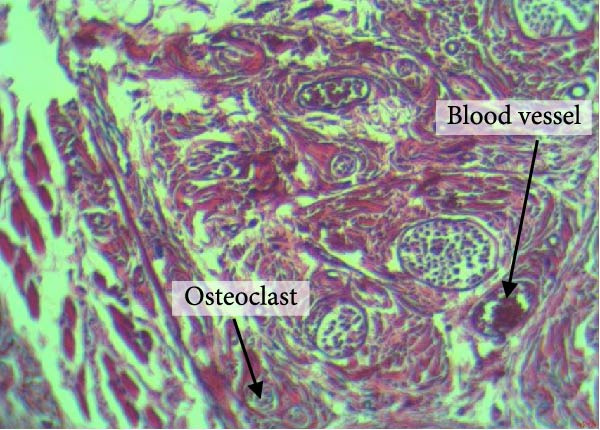

Figure 4 shows the periodontal tissue light‐microscopic findings in the study groups. As shown, the number of blood vessels, osteoclasts, and Howship’s lacunae was significantly higher in rats subjected to stress and CE injection for a 40‐day period, compared with others.

Figure 4H&E staining. Blood vessels and osteoclasts in different subgroups: (A) orthodontic treatment/CE injection/stress (chronic); (B) orthodontic treatment/CE injection/stress (acute); (C) no orthodontic treatment/CE injection/stress (chronic); (D) no orthodontic treatment/CE injection/stress (acute).(A)(B)(C)(D)